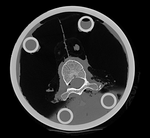

original unregistered unregistered

registered (after flipping axis and cropping volume) registered